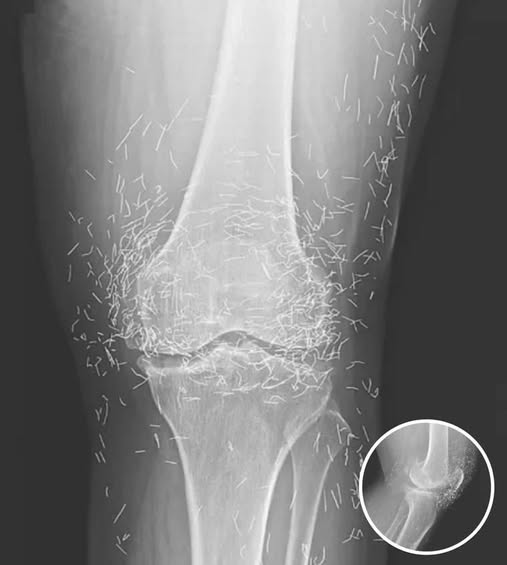

Doctors Stunned After Looking At This X-Ray Of Woman Suffering Joint Pain

A 65-year-old woman in South Korea experienced a shocking medical discovery when doctors found hundreds of tiny gold needles embedded in her knee tissue during a routine X-ray. She had …